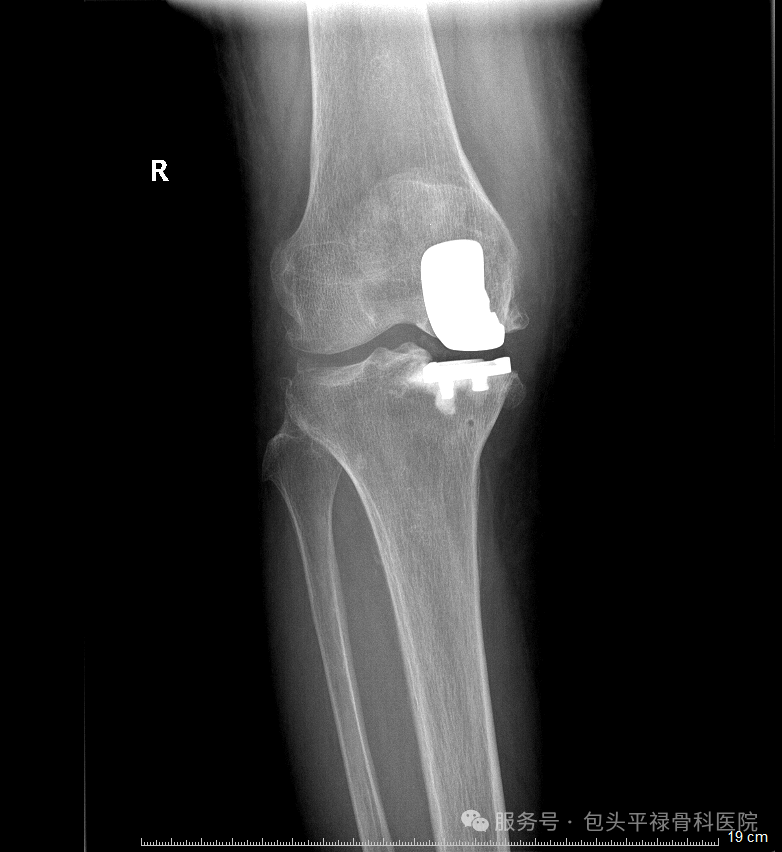

膝关节单髁置换术相当于“局部翻新”,就是只置换“坏掉房间”的磨损表面,仅将受损的软骨和部分骨质去除,替换为人工假体,而完好的软骨、交叉韧带及其他结构都得以最大程度的保留。

关节炎主要局限于膝关节的一个间室,其他间室和髌股关节软骨基本完好。

膝关节的前后交叉韧带、内外侧副韧带结构完整,功能良好。这是保证手术效果和关节稳定性的关键。